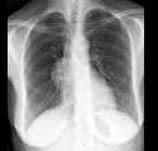

问题 根据图象提示,重症肌无力患者做X线胸片检察的目的是 ( )

选项 A、检察是否有膈肌麻痹 B、检察是否有胸腺瘤 C、检察是否有异位甲状腺 D、检察是否有肺结核 E、检察是否合并有肺部感染 一、单项选择题

答案 B